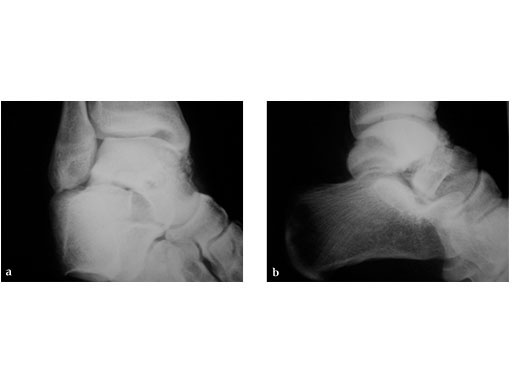

23-year-old male with moto cross accident

Case provided by P. Cronier, Angers, France

ORIF (day 5): Anteromedial approch and Ollier approach